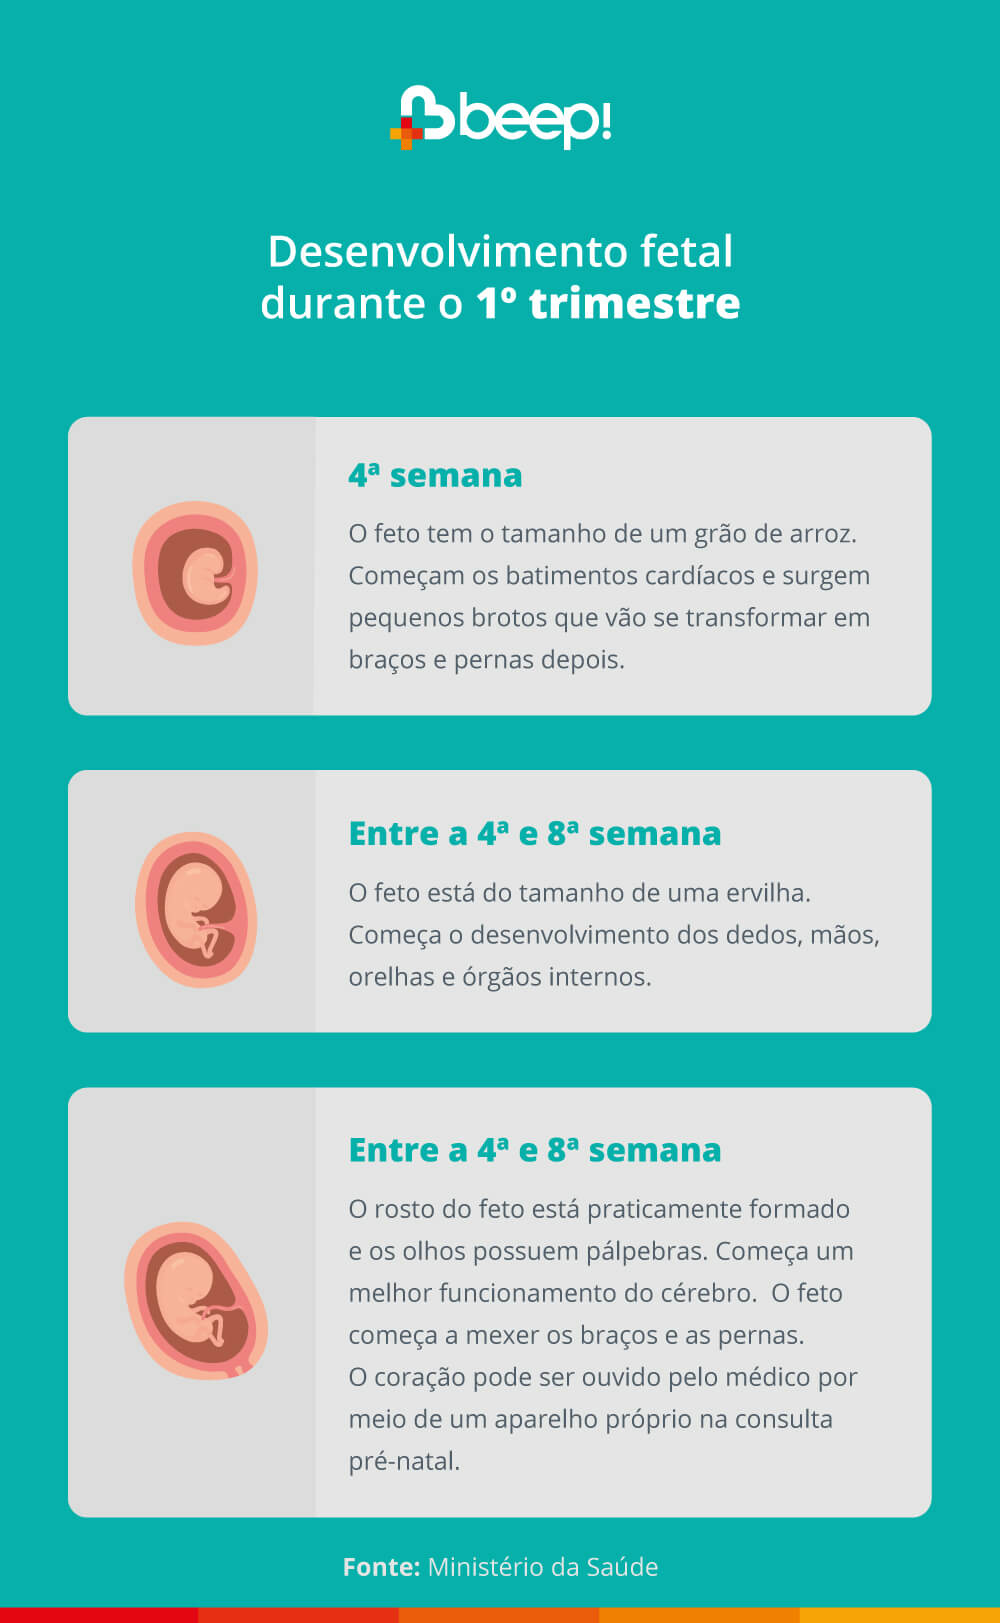

Assim como a gestante, o seu bebê também vai passar por muitas transformações até o nascimento. Veja cada uma delas!

Entre as principais mudanças estão: o crescimento do feto, desenvolvimento dos dedos, formação do rosto, entre outras. Veja em detalhes: